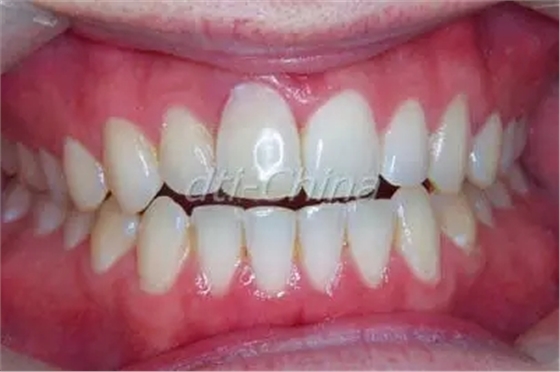

患者是一個30歲健康男性, 來診所檢查失去功能的上頜右中切牙, 過去在1993年的一次足球意外中因臉部受到肘擊導致上頜右中切牙的外傷,在事故大約一周之后, 對患者的牙齒進行了根管治療,最后牙齒開始變色而且越來越不整齊(圖1)。影像檢查發(fā)現(xiàn)內吸收。通過臨床診斷,發(fā)現(xiàn)所有其它的上下前牙都完好無損,牙周檢查顯示健康的牙齦組織,患者擔心他的前牙會意外斷裂, 并希望立即替換患牙。